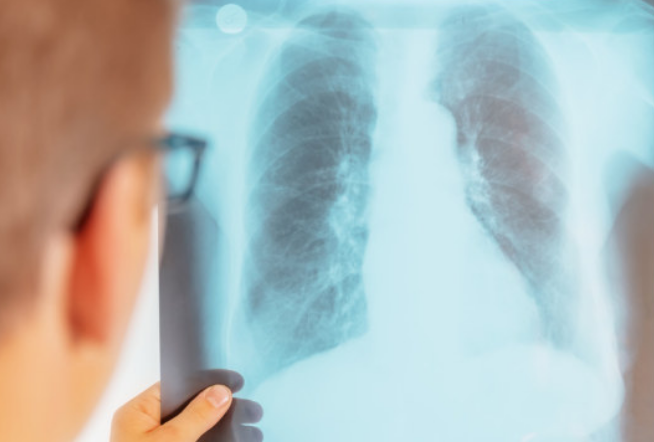

长结节是比较普遍的现象,如果用细致的影像检查的话,每个人身上或多或少都会发现一些结节。结节可能藏匿于皮下、肺部、乳腺、甲状腺、前列腺等各部位。它们大多没有症状,有的因为体积小且在体内,患者平时可能看不到也摸不着,直到体检时才发现。以常见的肺结节来说,粗略统计我国可能有1.2亿肺结节患者,其中8000万患者都是小于0.8厘米的小结节。

肺结节:可能是由于吸入过多灰尘等物理刺激或肺部炎症等,导致肺细胞过度增殖,“抱团儿”堆积到一起,就形成了肺结节。

张晓军指出,推断结节的性质要通过触诊结合影像检查。乳腺结节要靠彩超、钼靶、核磁等检查;甲状腺结节要靠彩超、CT、造影检查;超过1厘米的肺结节要拍胸片,小于1厘米的要做CT及核磁检查。